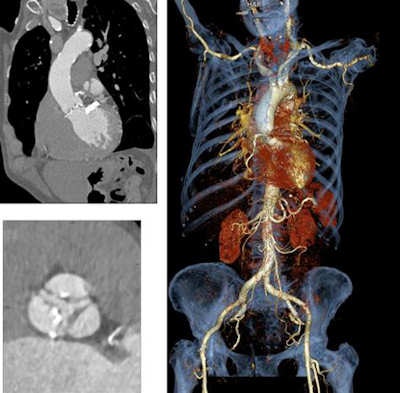

The comprehensive set of CT measurements required for TAVI planning with CT include the following:

- Assessment of aortic root

- Leaflet calcifications and vegetations

- Annulus sizing and matching specific device

- Size of aortic sinus

- Location of coronary artery ostia

Clinicians must also determine the best imaging plane while minimizing contrast use, determine the best access route for the procedure, and assess comorbidities while ensuring sufficient vessel size, Becker said.

"We derive the vessel diameters from the dataset and determine the angulation so we can determine the implantation later on," he said. "The workstation also helps us very much to display the access route and the course of the aortic arteries and [determine] whether the catheter and sheath can be pushed through the iliac arteries to perform the procedure at all."